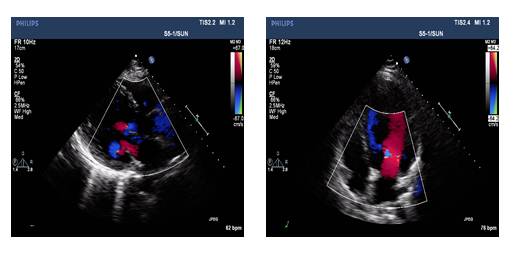

UCG(2014-5-14):

◆IVS 0.86cm, LVDd 6.4cm, EF 40%

◆轻-中度二尖瓣关闭不全

◆UCG: LVDd 5.7cm, LAD3.9cm, LVEF 50%, 轻中度二闭

◆UCG: LVDd 5.6cm, LVEF 53%

◆UCG: LVDd 5.65cm, LAD3.9cm, LVEF: 50%